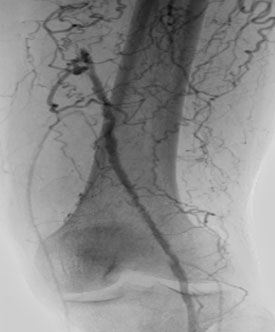

- Следующим этапом выполнена механическая реканализация и баллонная ангиопластика артерий голени.

Ангиографическая картина голени перед баллонной ангиопластикой |

| Ангиографическая картина после баллонной ангио пластики | |

Контрольная ангиография показала полный успех: герметичные швы, состоятельные анастомозы и, главное, – восстановленный кровоток по всем сосудам левой нижней конечности до пальцев.